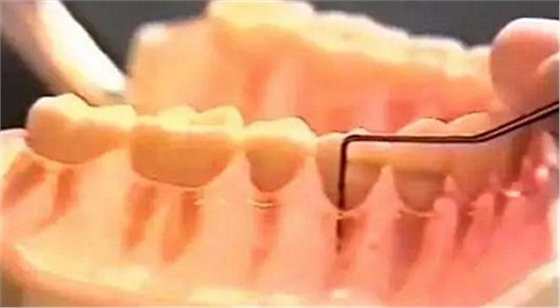

4、牙周探診

牙周探診是對牙周炎患者的最基本檢查技術(shù)之一。同一患者各個牙齒的牙周炎病情不同,同一患牙上的各個位點的牙周袋深度亦可不同,通過全口牙周探診可以較準確地了解病情。在探測袋深度時,還可通過BOP了解袋內(nèi)壁的炎癥程度、齦下牙石的多少等。原則上應(yīng)對每位患者篩查其有無牙周炎,可重點探診牙齒鄰面,有無牙周袋和探診后出血;牙周專科檢查時,應(yīng)對每個牙的多個位點進行探查。

操作方法:

(1)應(yīng)使用鈍頭帶刻度的牙周探針。

(2)探針須與牙長軸平行,探針的尖端緊貼牙面,探入袋底后記錄從袋底到齦緣的距離(mm),即探診深度。探鄰面時探針緊靠接觸區(qū),尖端可略向鄰面中央傾斜。

(3)探查同一牙面較寬的牙周袋時,應(yīng)提插式移動,以探明不同深度的牙周袋狀況。

(4)探診時支點要放穩(wěn),用力不可過大,力量掌握在20~25g。

(5)探測牙周附著水平時,必須要找準釉牙骨質(zhì)界位置,才能測量準確。記錄袋底到釉牙骨質(zhì)界的距離,即為附著喪失程度;若該牙有牙齦退縮,則附著喪失程度是只指牙齦退縮的毫米數(shù)加上袋底到齦緣的距離。

(6)探診后應(yīng)記錄是否出血,即BOP陽性與否。